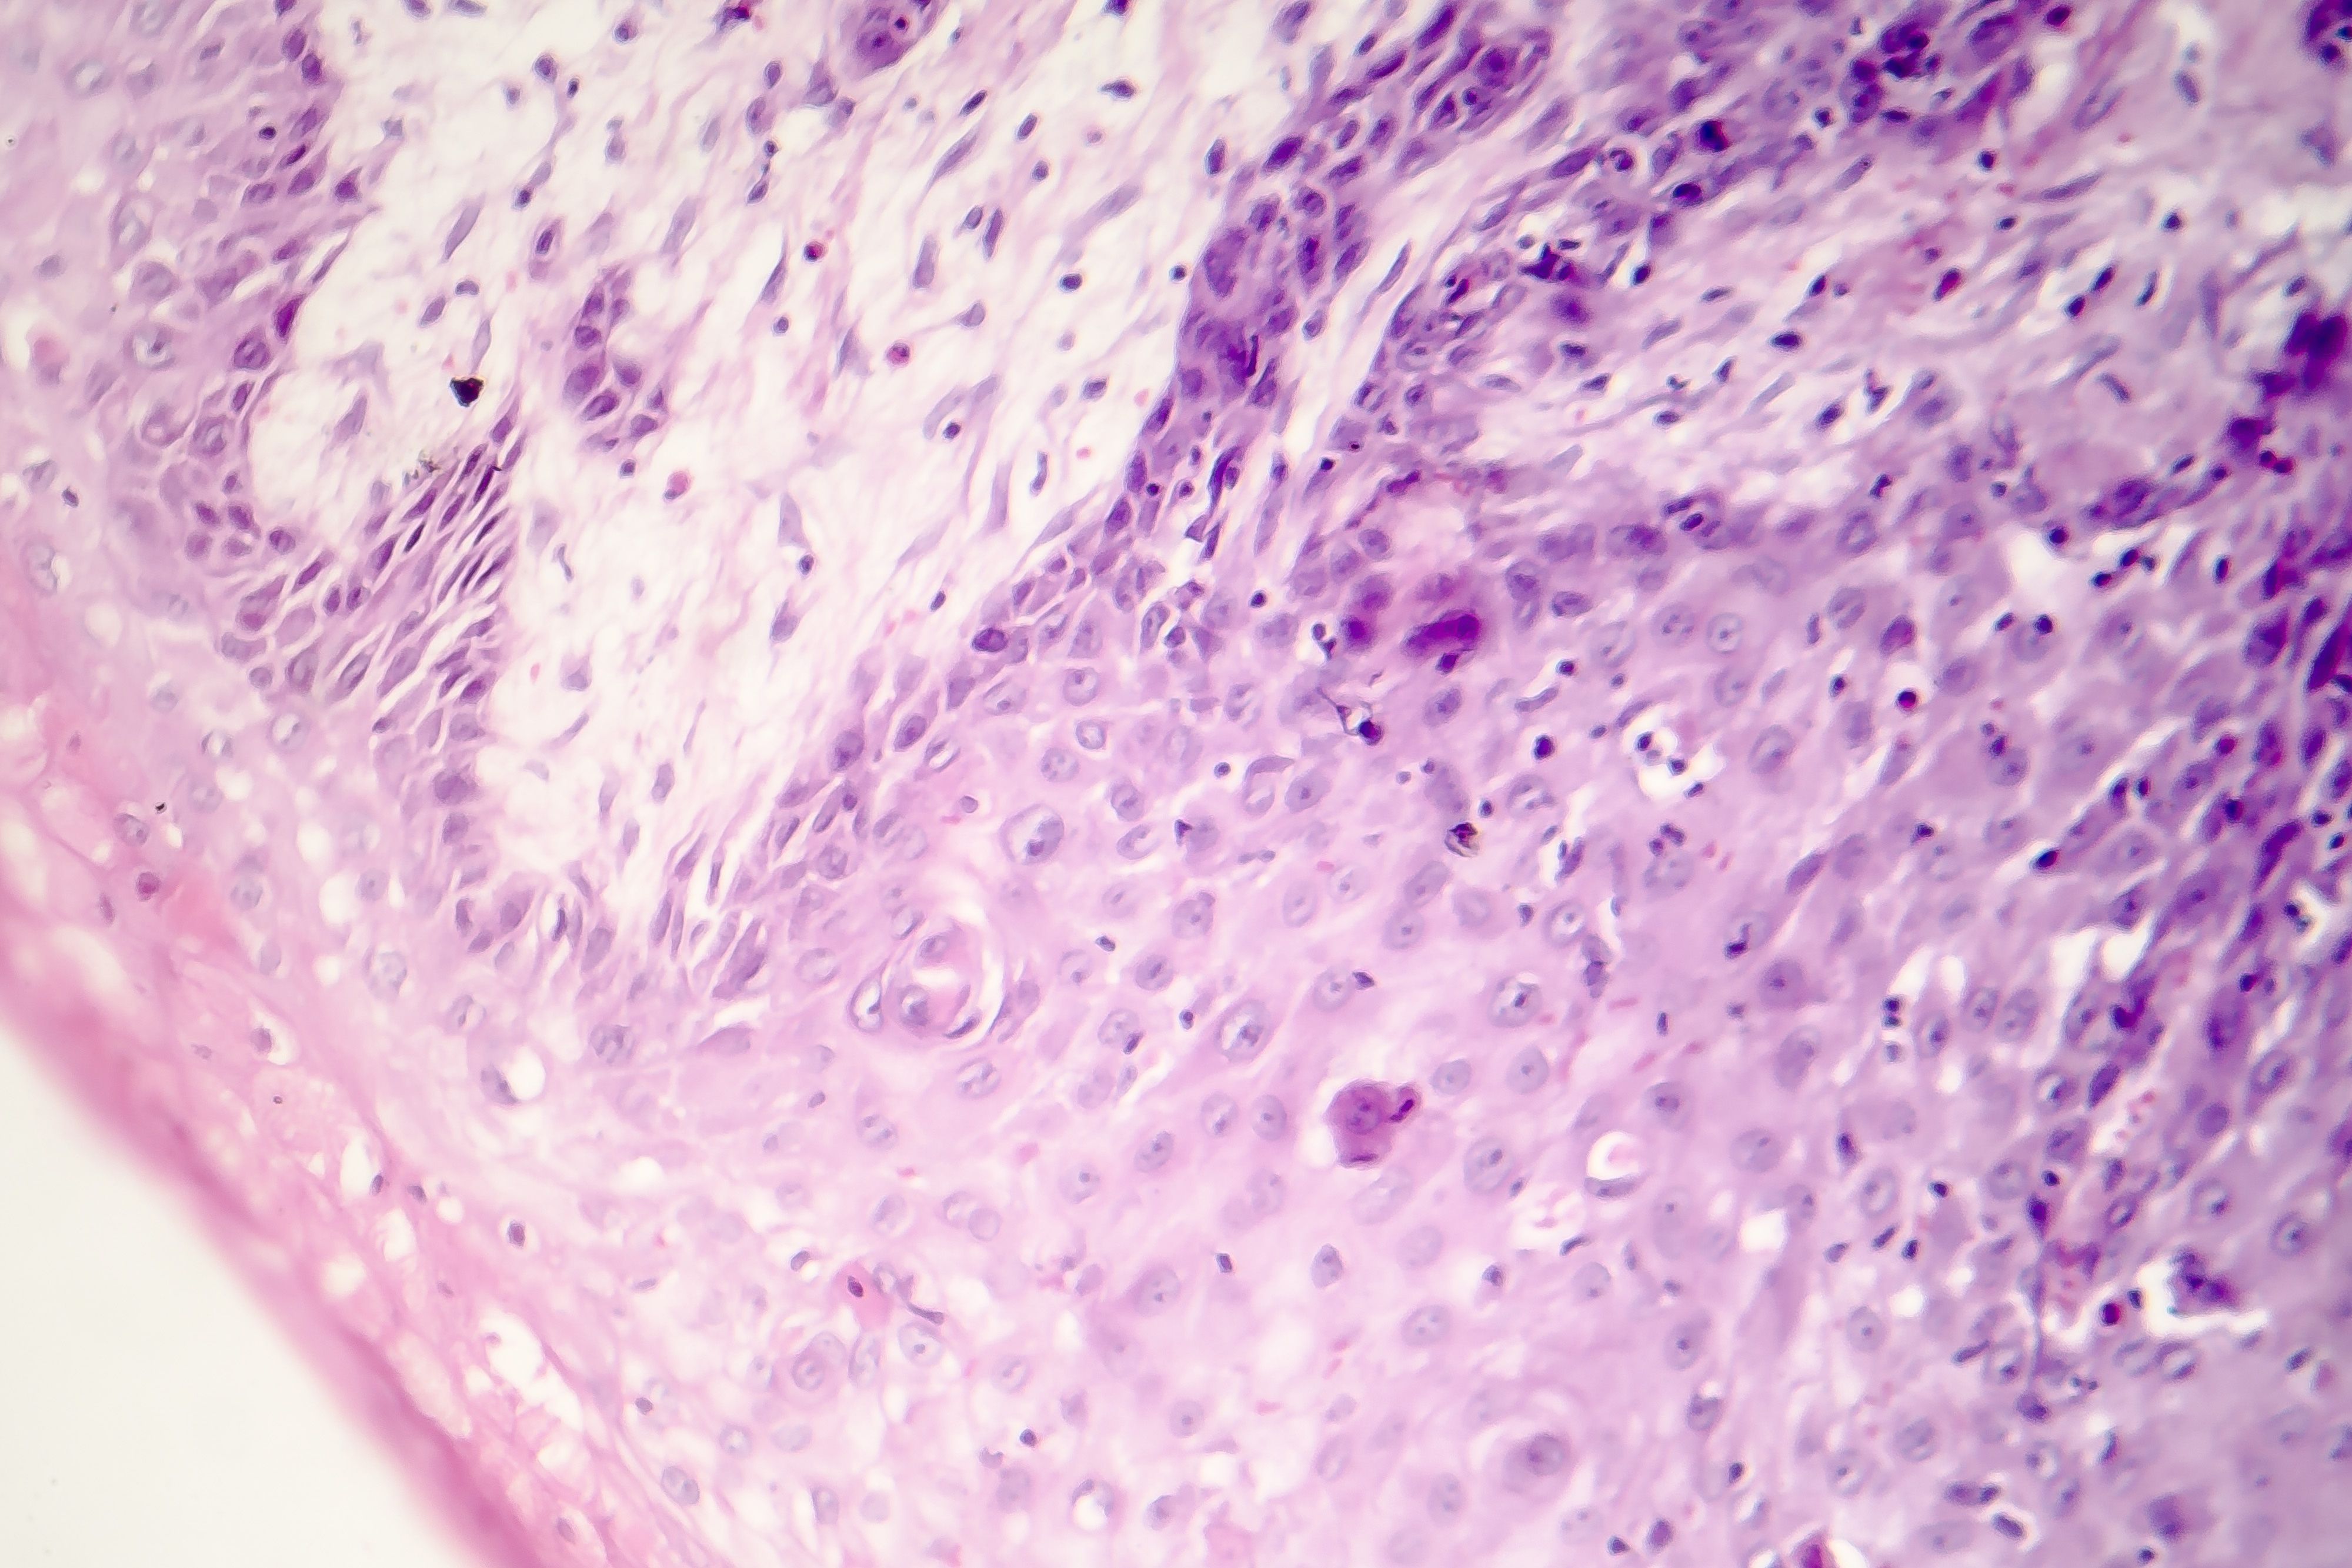

A Showing Grade 3 (poorly differentiated) SCC (H&E x20). B

No / Minimal Keratinization, Marked Nuclear Atypia, May Be Difficult To Establish Squamous Differentiation.

Poorly Differentiated Scc - For this type of scc, immunostains will likely be required to classify. For this type of scc, immunostains will likely be required to classify. No / minimal keratinization, marked nuclear atypia, may be difficult to establish squamous differentiation. Poorly differentiated squamous cell carcinoma. Poorly differentiated sccs are dermoscopically typified by a predominantly.

No / minimal keratinization, marked nuclear atypia, may be difficult to establish squamous differentiation. Poorly differentiated squamous cell carcinoma. For this type of scc, immunostains will likely be required to classify. Poorly differentiated sccs are dermoscopically typified by a predominantly. For this type of scc, immunostains will likely be required to classify.